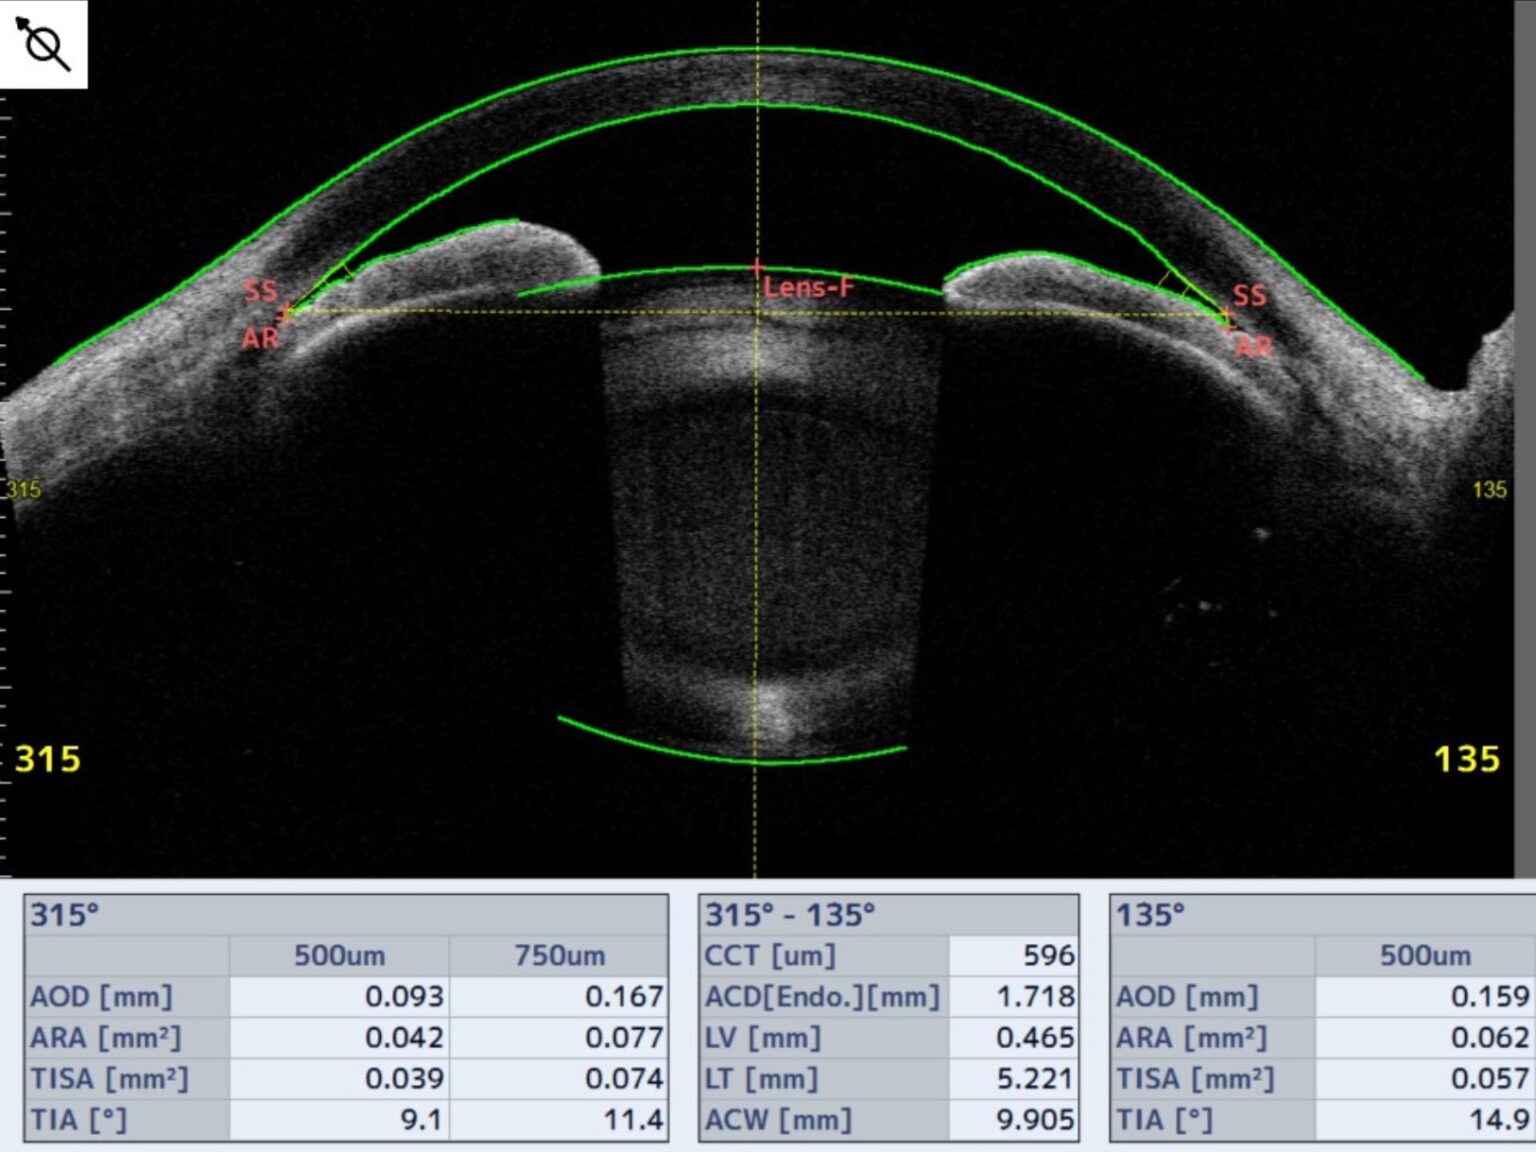

閉塞隅角緑内障の場合、眼から液体が正常に流れ出ないため、圧力が高まります。

液体は、虹彩の後ろの眼の後房で生成されます。この液体は通常、瞳孔を通って眼球の前房に流れ込みます。

次に、液体は小柱網と呼ばれる一連のチャネルを通って、強膜 (白目) の静脈に流れ込みます。

閉塞隅角緑内障では、小柱網が閉塞または損傷します。液体はこの排水経路を容易に通過できないか、完全にブロックされています。この液体のバックアップにより、眼球内の圧力が上昇します。

原発性閉塞隅角緑内障では、目の構造により虹彩が線維柱帯に押し付けられる可能性が高くなります。これは次の理由が考えられます。

- 虹彩と角膜の間の角度は非常に狭い

- 眼球は前から後ろに測ると比較的短いです

- 目の中の水晶体が厚く、虹彩が前方に押し出される

- 虹彩が薄いため、角に折れ曲がっています